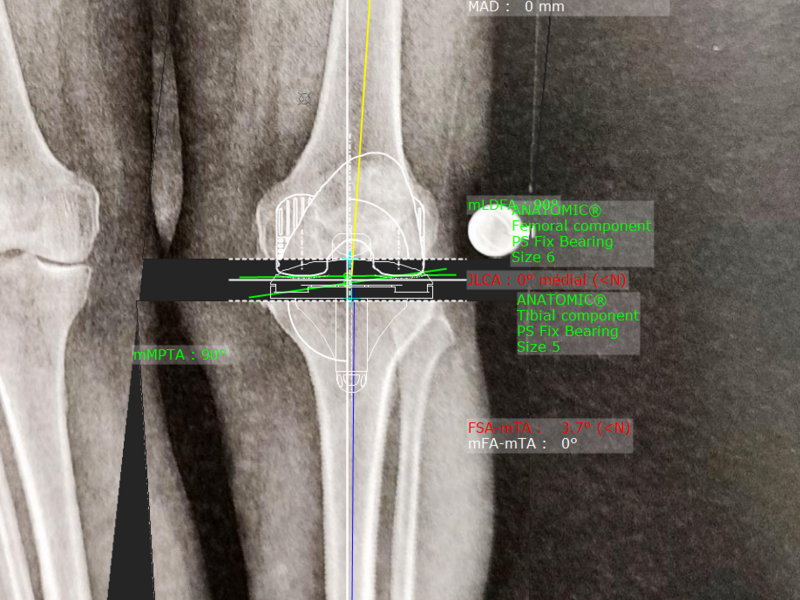

Album photo